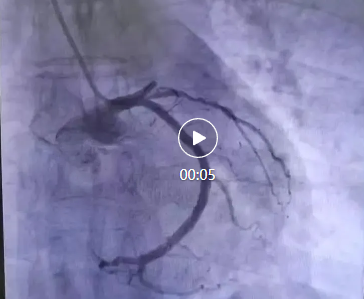

醫(yī)院立即啟動了胸痛中心綠色通道。心血管內科李桂武主任、劉興剛主任迅速到位,患者瀕臨崩潰的問道:“大夫,我能活么,孩子媽媽雙目失明,還有倆孩子20歲不到,我要死了,這個家就完了”,李主任、劉主任握著患者的手堅定地說道:“我們的目的不僅僅是讓您活著,還要讓您更有質量的生活,所以你要堅持,相信我們?!彪S即,李主任、劉主任為張先生進行了冠狀動脈造影,結果顯示,張先生的前降支近段完全閉塞,這是導致他胸痛的直接原因。李主任當機立斷,決定進行急診冠脈支架植入術。

手術過程非常順利。醫(yī)生通過導管將支架送至閉塞部位,成功開通了阻塞的血管,恢復了心肌的血液供應。術后,張先生的胸痛明顯減輕,呼吸也逐漸平穩(wěn)。被轉入心臟重癥監(jiān)護室(CCU)進行密切觀察。醫(yī)生為他制定了詳細的治療方案,包括抗血小板藥物、他汀類藥物、β受體阻滯劑等,以預防血栓再形成、穩(wěn)定斑塊并降低心臟負荷。!